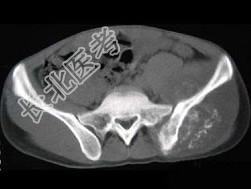

- 单项选择题男,35岁, 左髂部剧烈疼痛,尤以夜间明显, 可摸到肿物,结合图像, 最可能的诊断是 ( )

A、骨巨细胞瘤

B、软骨肉瘤

C、骨转移瘤

D、骨肉瘤

E、软骨瘤